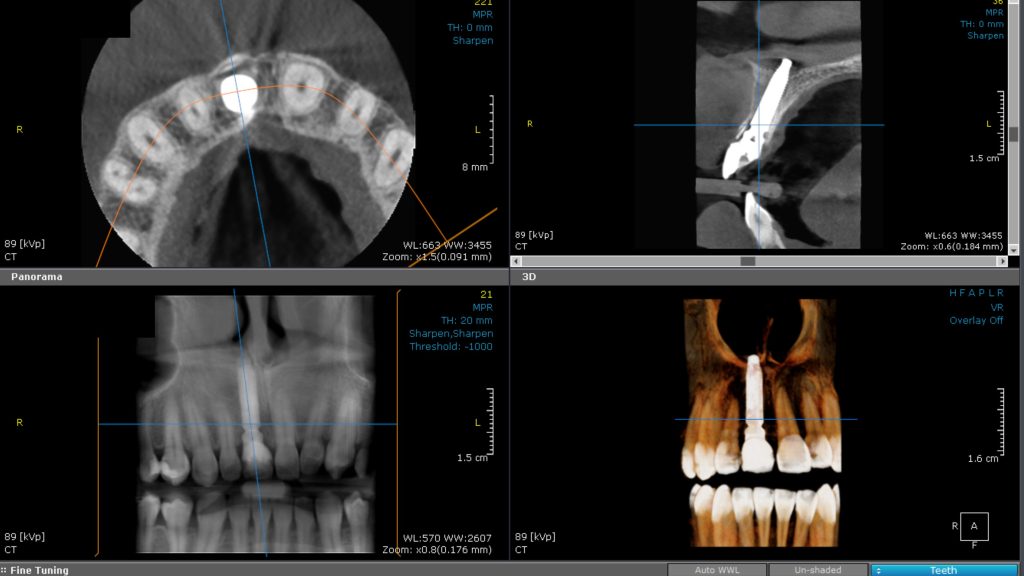

Surgical stage